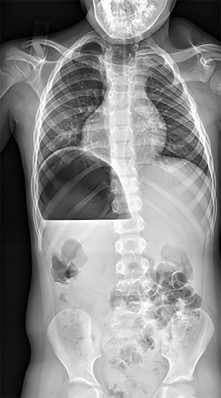

A 25-year-old male is involved in a high-speed motor vehicle collision. Radiographs demonstrate a traumatic spondylolisthesis of the axis (Hangman's fracture) with an oblique fracture line through the pars interarticularis, minimal translation, but extreme angulation (>11 degrees). The C2-C3 disc space appears disrupted posteriorly. According to the Levine-Edwards classification, what is the most appropriate initial management for this specific injury pattern (Type IIa)?

The scenario describes a Levine-Edwards Type IIa Hangman's fracture. This injury is caused by a flexion-distraction mechanism, leading to severe angulation with minimal initial translation. A critical point in management is that axial traction is STRICTLY CONTRAINDICATED, as it will exacerbate the distraction and worsen the deformity. The appropriate non-operative management involves the application of a halo vest under gentle compression and extension to reduce the angulation and stabilize the fracture.